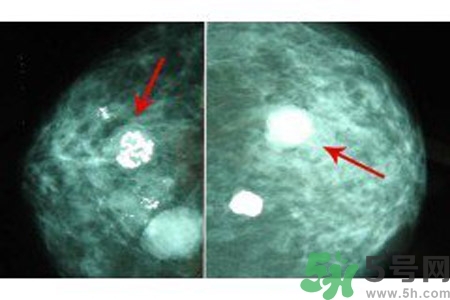

良性惡性乳腺增生鈣化的差異

與良性乳腺增生鈣化相比,惡性乳腺增生鈣化群平均密度較低,密度及大小對(duì)乳腺疾病良惡性鑒別價(jià)值較大。乳腺X線片中微小鈣化分布似乎無規(guī)律可循,但病理發(fā)現(xiàn)癌腫發(fā)生于末梢導(dǎo)管時(shí),鈣化可位于大片壞死組織中或癌細(xì)胞間,亦可存在于所屬上級(jí)導(dǎo)管內(nèi)或?qū)Ч芊植嫣幓蛳噜徬倥萸粌?nèi)。